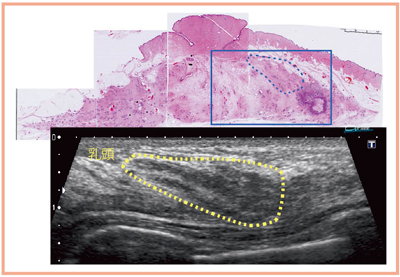

乳がん検診にあたり,以前はメカニカルセクタ方式の10MHzの超音波診断装置を使用していたが,当時でも3〜5mm程度の非浸潤性乳管癌(DCIS)や浸潤癌を見つけることは可能であった。しかし,乳腺外科を志してから3年目,乳腺症と診断した症例が,1年後にDCISであったことが判明し,乳房全摘再建術となった例を経験した(図1)。小さくても腫瘤性病変であれば検出は可能だが,非腫瘤性病変は低エコーを呈し,ある程度の厚みを持たないと検出が困難であった。そこで,非腫瘤性病変をできるかぎり小さいうちに検出することをめざし,さまざまな症例を観察した結果,正常乳腺の雲のように流れる縞模様を目で追っていくと,小さな非腫瘤性病変でも,その規則性が乱れたところで見つけられるのではないかと考えるようになった(図2)。しかも,高分解能超音波では乳腺の正常構造がよりクリアに見えることから,この観察法の有効性がより発揮されていると実感している。

図1 乳腺症と診断した症例が,1年後にDCISと判明した例